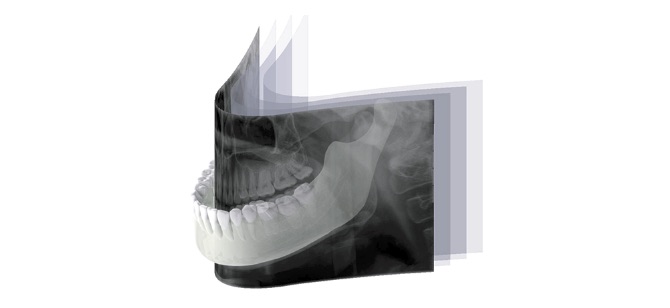

「オートフォーカス」はパノラマモード専用の機能です。焦点が合う最適な部分を自動で抽出して画像を生成します。位置付けの失敗による再撮影のリスクも軽減されます。